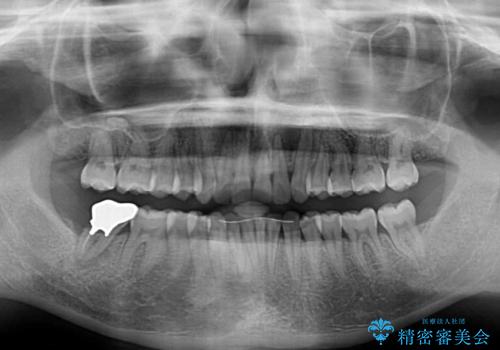

カリエールディスタライザーや部分的なワイヤー矯正を併用したことで、確実かつ短期間で治療を終えることができました。